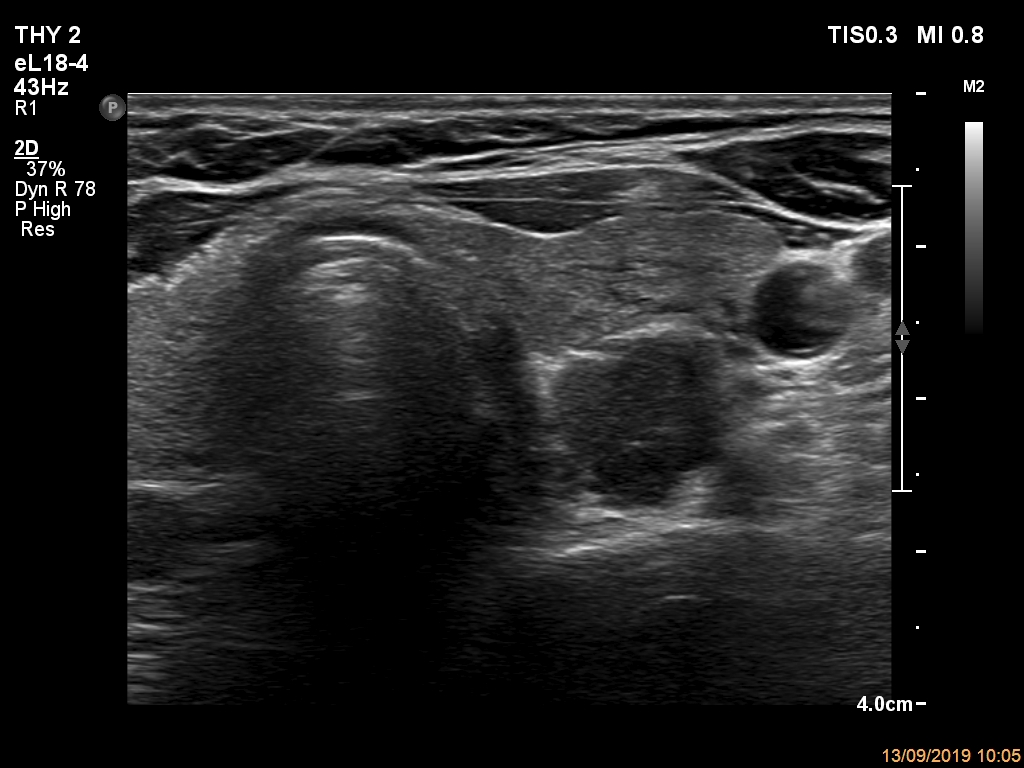

Right lobe, longitudinal scan

Left lobe, another transverse view. The dorsolateral part presents spiculated margins.